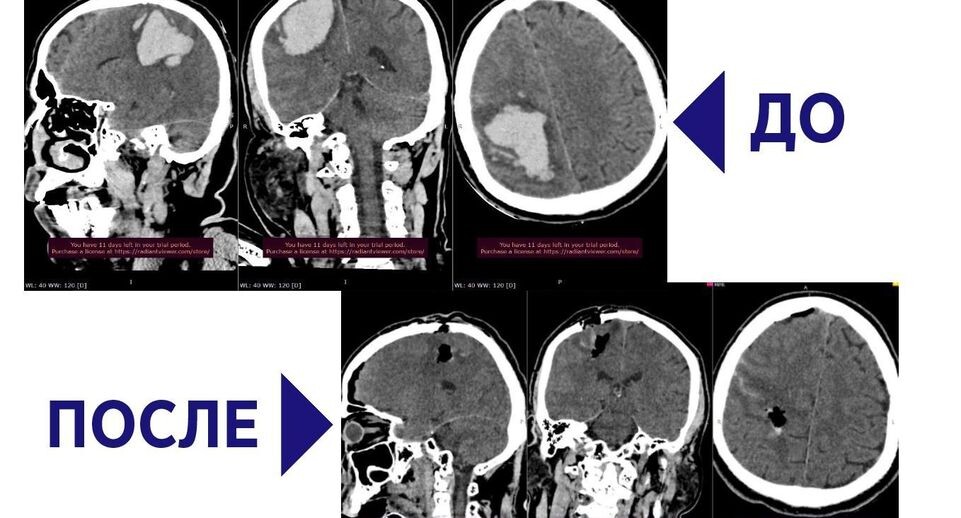

Врачи Сергиево-Посадской больницы спасли 56-летнего мужчину с крупной внутримозговой гематомой. В медицинское учреждение его привезли в состоянии комы.

Специалисты провели пациенту компьютерную томографию и обнаружили гематому объемом почти 70 миллилитров, возникшую в результате геморрагического инсульта. Мужчине потребовалась экстренная операция, в рамках которой использовалось новейшее нейрохирургическое оборудование.

«Гематома из себя представляла несколько крупных сгустков, которые последовательно были извлечены при помощи аспиратора. Через несколько часов пациент пришел в сознание. Речевые и двигательные функции начали возвращаться», — пояснил врач-нейрохирург Сергиево-Посадской больницы Амрах Магеррамов.

По словам специалиста, вмешательство оказалось своевременным, так как состояние пациента ухудшалось с каждой минутой.

Через 10 дней мужчину выписали с удовлетворительным самочувствием. Ему предстоит пройти реабилитацию.